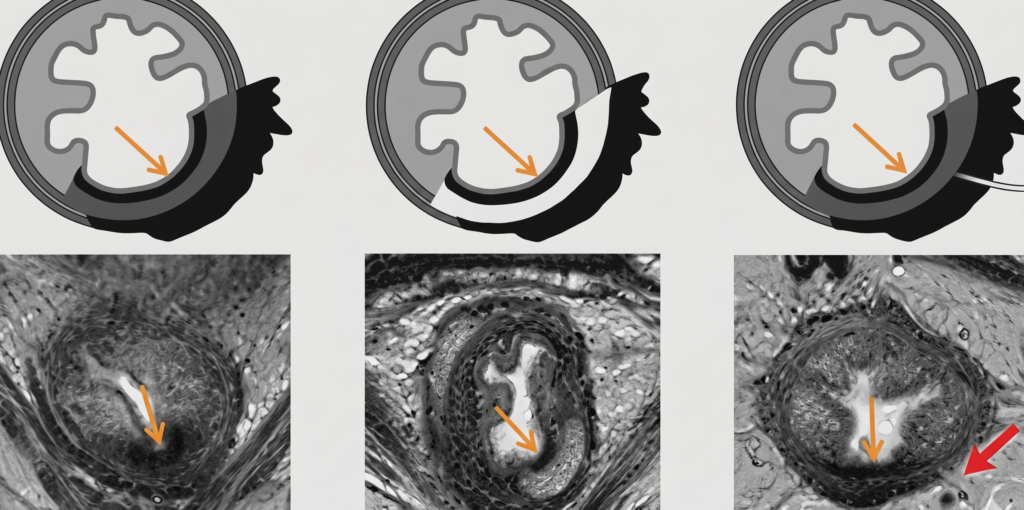

The Thin Black Line—Split Scar Sign on Rectal MRI

To determine if a split scar sign is positive, simply use the continuous line rule.